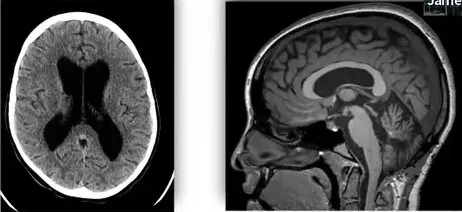

多年前,欢欢被确诊患有脑干胶质瘤。母亲初闻诊断时表现平静,但随后意识到病情的严重性。第三次就诊时,医生明确告知脑干手术难度大、风险高,术后效果不确定,若不能完全切除还需后续治疗,这让母亲难以继续逃避现实。

在此期间,患者病情急剧恶化:初期出现眼球转动受限(核间眼肌麻痹),随后快速发展为严重共济失调和右侧肢体无力,直至丧失独立行走能力。继而出现吞咽功能障碍和左侧面瘫,最终生活完全不能自理。

他们特意求助多伦多大学儿童病院、亚瑟和索尼亚拉巴特脑瘤研究中心主任James T.Rutka教授。该专家在儿童脑干胶质瘤领域具有丰富经验,能制定包括后续辅助治疗在内的完整治疗方案,使家属倍感安心。

教授评估后承诺将全力安全切除肿瘤,并避免严重并发症。家属在医院附近安顿下来,患者顺利住院,不久便迎来了期待已久的手术。